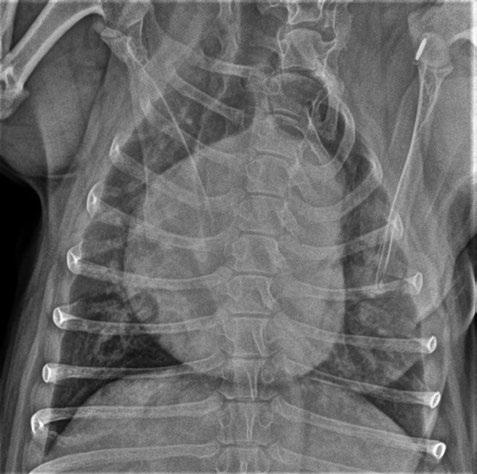

Bloqueantes de canales del calcio Hidralazina, nitratos e IECA